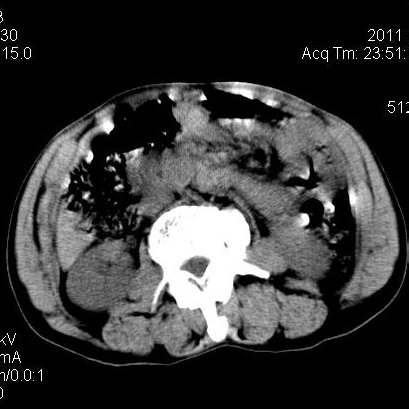

肝左叶发育异常

男性,55岁,骑摩托车摔倒后入院,自述右上腹疼痛

[backcolor=#FF0000]第一次诊断的时候也是这么肯定,可是床旁超声检查并没有发现明显异常,而且患者的一般症状都良好。还好临床只是保守治疗,没有立即手术,第二次复查的时候没有一点变化,又做了MRI检查,没有血肿,

这是一例肝左叶发育异常的,很个性吧~[/backcolor]